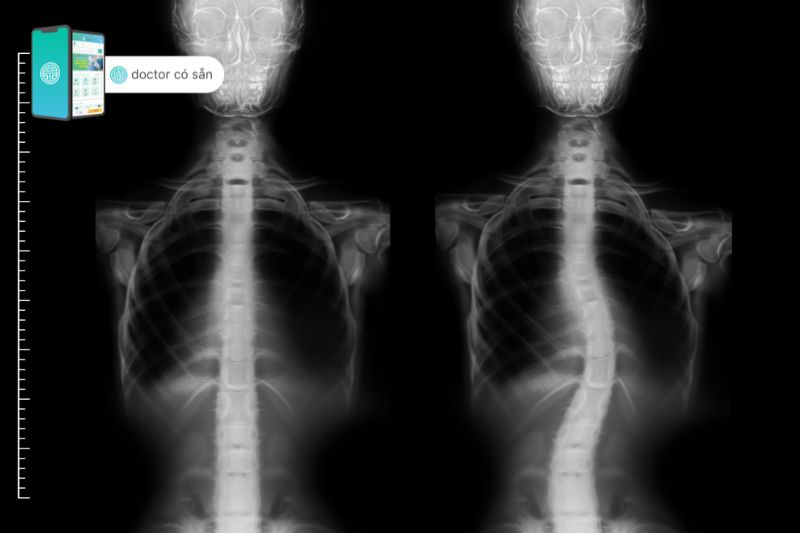

Trước khi đưa ra quyết định phương pháp trị liệu cho những trường hợp vẹo cột sống thì các bác sĩ hoặc chuyên gia y tế phải chẩn đoán, xác định mức độ của tật vẹo cột sống của người bệnh. Các phương pháp chẩn đoán phổ biến thường được dùng như:

- Thăm hỏi về tiền sử bệnh lúc người mẹ lúc sinh con có gặp các tổn thương về thần kinh và cơ bắp hay không.

- Dựa trên những quan sát lâm sàng bên ngoài có thể thấy được độ lệch cũng như mức độ cong vẹo cột sống nhẹ hay nặng, các vùng cơ bị teo (cơ trap trên, cơ trap dưới ở vùng vai lưng,…), các dị tật, tổn thương có thể thấy được.

- Dựa trên chụp ảnh X-quang sẽ xác định được độ lớn của góc cong vẹo cột sống (góc Cobb). Tuỳ theo độ lớn góc Cobb và khả năng tiến triển mà các bác sĩ sẽ chỉ định các phương pháp phục hồi chức năng hay mang áo nẹp. Nếu vẹo cột sống nặng và tiến triển nhanh thì sẽ phải chỉ định phẫu thuật chỉnh hình.

- Đôi khi nếu cần thiết cần khảo sát thêm chụp CT scan cột sống, MRI cột sống, MRI não, điện não, xét nghiệm gen,… để tìm nguyên nhân của vẹo cột sống.